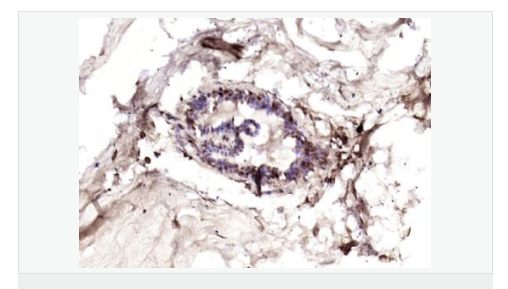

交叉反應:Human(predicted:Mouse,Rat) 推薦應用:IHC-P,IHC-F,IF,ELISA

| 產品應用 | ELISA=1:5000-10000 IHC-P=1:100-500 IHC-F=1:100-500 IF=1:100-500 (石蠟切片需做抗原修復) not yet tested in other applications. optimal dilutions/concentrations should be determined by the end user. |

| 細胞定位 | 細胞核 細胞漿 細胞膜 |